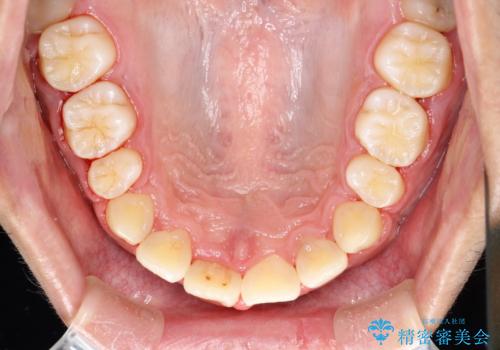

ワイヤー矯正終了時に装置除去と合わせてPMTC

- ワイヤー矯正の終了時にしばらく行っていないためクリーニングも希望されました。装置の除去j時にPMTC60分コースを行いました。

装置を除去すると、エナメル質にダメージがかかることなどがあります。除去の際、一緒にクリーニングを行うことで、エナメル質をなめらかにしたり、歯ぐきの引き締まりが見られます。また、歯ブラシだけでは取り除けない汚れも取り除きますので、歯の表面がツルツルになります。矯正治療中・終了時には合わせてPMTCを行うことがおすすめです。